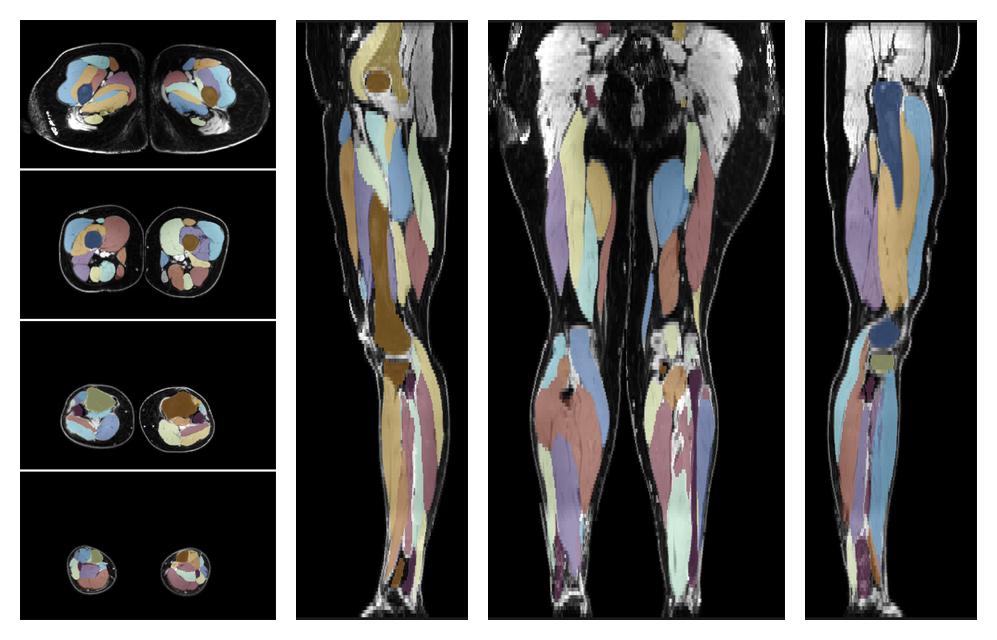

Muscle segmentation

Convolution neural network based (UNET) fiber automated muscle segmentation, for information look here».

• Automated muscle and bone segmentation.

Overlay of automated muscle segmentation labels on dixon water image.